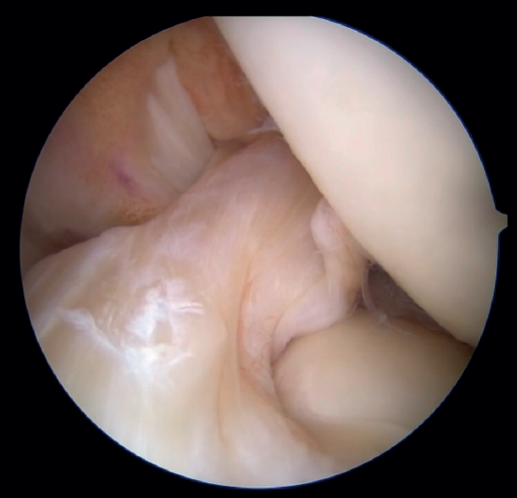

The patient is placed in the supine position and the leg is draped and prepared for knee arthroscopy at the surgeon's discretion, as if an ACL plasty were to be performed. The anterolateral and anteromedial portals are established as usual, and the joint is explored. On exploring the central compartment, it should be confirmed by direct vision and also palpation that the lesion is proximal and that the tissue quality is good; if the tissue is friable and tears easily, repair is not indicated. If the ACL remnant is attached to the PCL, it must be dissected so that the ACL is free and can be manipulated to its insertion site. A blunt shoulder arthroscopy periosteotome is best used for this, although a synoviotome, vaporizer or plasma applicator could also be used, as long as care is taken not to break or burn the tissue and render it non-viable. If there are concomitant meniscal or cartilage lesions, they should be treated earlier in order to avoid forced varus and valgus positions after the repair is completed.

The patient can be placed in the position each surgeon prefers for ACL reconstruction surgery. As with the direct fixation technique, this procedure begins by using the usual anterior portals in knee arthroscopy: a high, anterolateral portal and a standard anteromedial portal. Similarly, the ACL is examined with a palpator to confirm the tear and its suitability for repair.